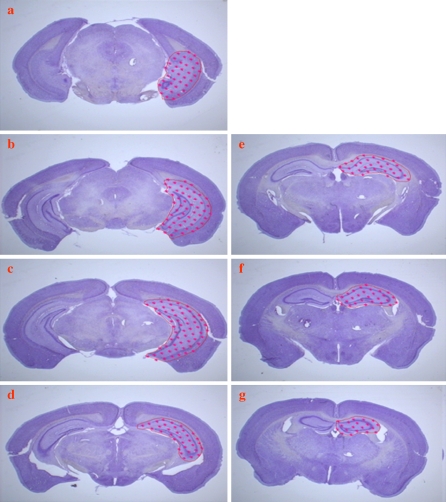

Fig. 2.

a–g Low power photomicrographs of serial sections through the entire mouse hippocampus; sections were cut at an instrument setting of 50 μm and stained with CV

Using the Cavalieri-point counting method, VHF and Vbrain were quantified on systematic-random samples of MRI images and histology sections from dtg APP/PS1 and WT controls (Figs. 1 and 2). No genotype-based differences were observed in either hippocampus or whole brain volumes from MRI images of dtg APP/PS1 mice [VHF= 30.4 (0.12) mm3, Vbrain= 451.5 (4.31) mm3, parenthesis represent (SEM)] compared to that for WT controls [VHF=30.7 (0.66) mm3, Vbrain= 449.6 (0.54) mm3]. Similarly, the analyses on histological sections revealed no genotype effects on VHF and Vbrain, with average volumes in the dtg APP/PS1 mice [VHF 4.6 (0.12) mm3, Vbrain = 61.5 (1.12) mm3] comparable to that for the WT controls [VHF = 4.8 (0.13) mm3, Vbrain = 60.2 (2.05) mm3]. Comparison of the ratio of hippocampus to whole brain volumes [(mean VHF/ mean Vbrain) •100] showed no differences for volume estimates on MRI images (dtg APP/PS1 = 6.73% vs. WT = 6.83%) or histological sections (dtg APP/PS1 = 7.48% vs. WT = 7.97%). The effects of agonal and tissue processing reduced the average volumes in histological sections by about 84–87% of the same volumes in MRI images.